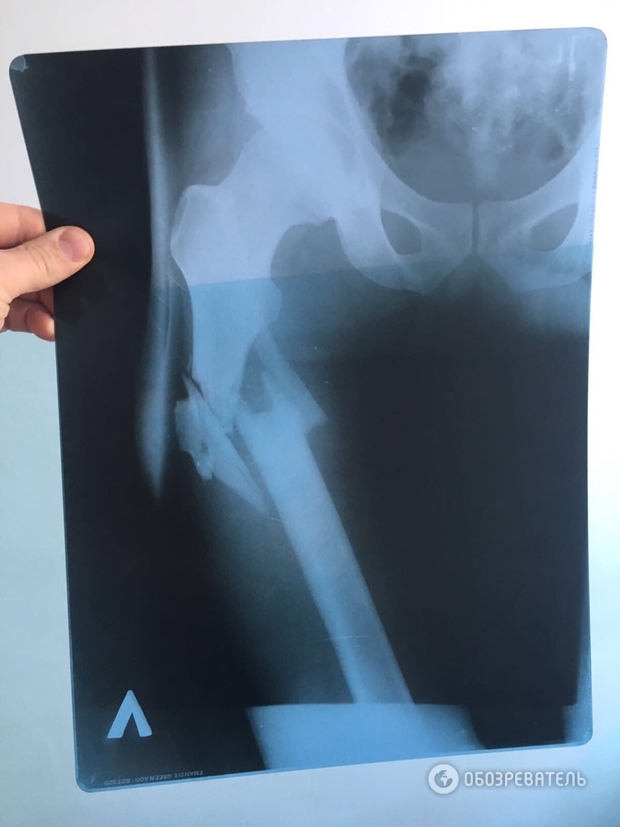

Врач, оперировавший Вячеслава Химикуса, которого ранил из пистолета народный депутат Сергей Пашинский, на допросе подтвердил, что на месте перелома у пострадавшего обломки кости смещены вниз от таза. Об этом "Обозревателю" сообщил собственный источник.

Он также подчеркнул, что данный факт подтверждает, что Пашинский выстрелил сверху в ногу Химикусу, а не из положения лежа, как нардеп утверждал ранее.

Напомним, "Обозревателю" удалось заполучить также рентгеновский снимок простреленной ноги Химикуса и заснять пулевые отверстия на его штанах. Учитывая положение входного и выходного отверстий от пули, можно предположить, что пуля "шла" сверху вниз.